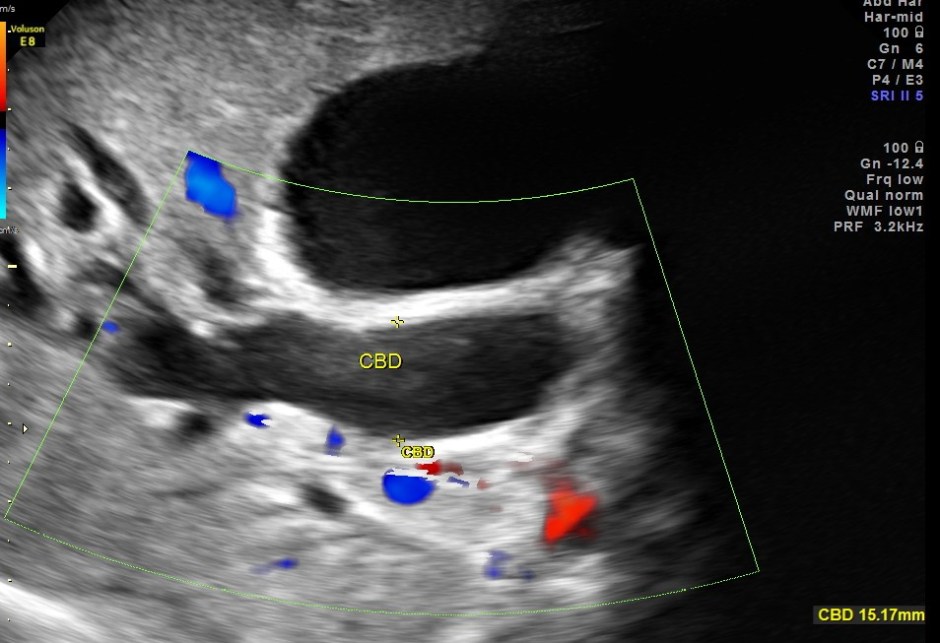

Courvoisier’s law (or Courvoisier syndrome, or Courvoisier’s sign or Courvoisier-Terrier’s sign) states that in the presence of an enlarged gallbladder which is nontender and accompanied with mild jaundice, the cause is unlikely to be gallstones. Usually, the term is used to describe the physical examination finding of the right-upper quadrant of the abdomen. This sign implicated possible malignancy of the gall bladder or pancreas and the swelling is unlikely due to gallstones.

This was a 55 year old man with history of jaundice and upper abdominal pain .